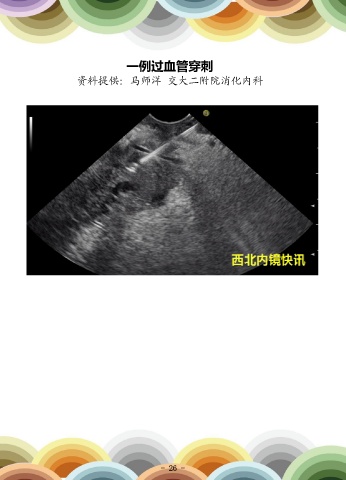

一例过血管穿刺                                                             一例幽门部肿瘤脱入十二指肠球部

资料提供:马师洋 交大二附院消化内科                                                           资料提供:张排旗             西安市第三医院消化内科